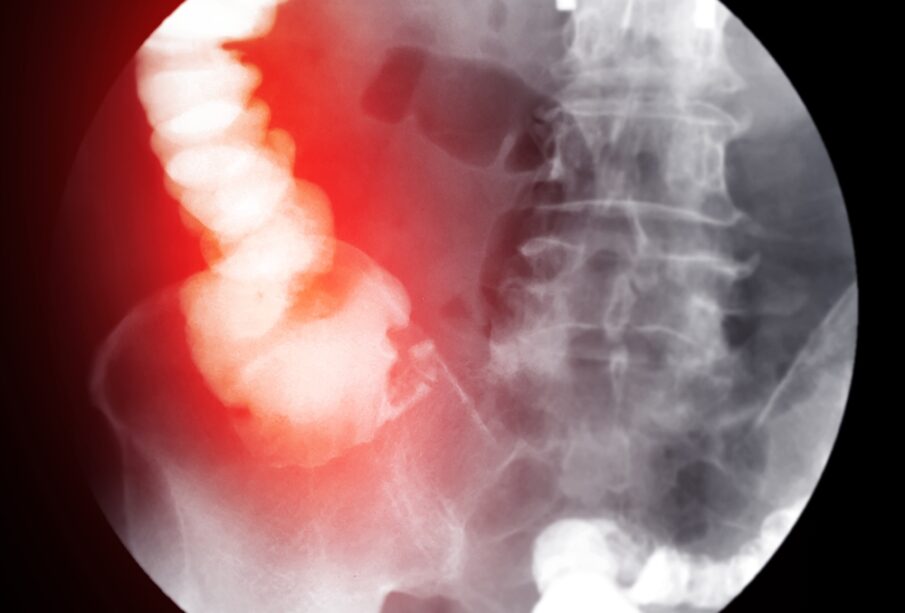

Ο ειλεός είναι μια κατάσταση κατά την οποία διαταράσσεται η φυσιολογική προώθηση της τροφής μέσα στο έντερο, με αποτέλεσμα το περιεχόμενο της πέψης να συσσωρεύεται και να μπορεί να προκαλέσει απόφραξη. Σε ορισμένες περιπτώσεις, το πρόβλημα αυτό μπορεί να οδηγήσει σε σοβαρές επιπτώσεις για την υγεία, όταν το εγκλωβισμένο περιεχόμενο σταματήσει πλήρως τη λειτουργία του εντέρου.